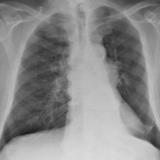

SCLC

Album: SCLC

Date: 10/01/2006

Size: 3 items

Views: 30634